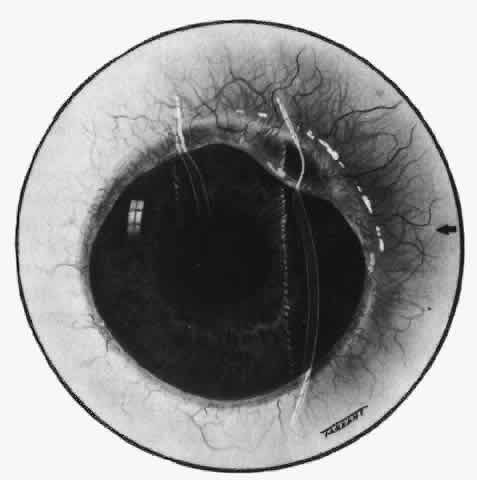

Simple and nodular episcleritis differ in their clinical courses, but in both the edema and infiltration are entirely within the episcleral tissues. The sclera is not involved. The maximum congestion is in the superficial episcleral network, with some slight congestion of the conjunctival vessels and deep episcleral vessels (Fig. 10). The intraocular structures are not involved in either variety, nor is the visual acuity affected. Anterior segment fluorescein angiography reveals a normal vascular pattern but a very rapid flow rate, with the whole transit of the dye being completed within 2 or 3 seconds (Figs. 11 and 12).

Fig. 10. Maximum congestion in the superficial vascular plexus in episcleritis. The conjunctival and deep episcleral networks are separated from the deep plexus by edema and infiltration in the episcleral tissue. (Watson PG, Hayreh S, Awdry P: Episcleritis and scleritis. Br J Ophthalmol 52(3):278–279, 1968)

The redness of simple episcleritis may be intense, varying from a fiery-red or a brick-red discoloration to a mild red flush, but it does not have the bluish tinge that is seen in scleritis. The distribution is usually sectorial but can involve the whole anterior segment of the globe. The episcleral vessels are engorged but retain their normal radial position and architecture (Figs. 13 and 14; Color Plate 1A). In simple episcleritis, there is a diffuse edema of the episcleral tissues. These tissues are sometimes infiltrated with gray deposits that appear yellow in red-free light. Surprisingly, the eye is rarely tender to the touch.

Fig. 13. Infiltration of the episclera in which the superficial episcleral vessels show maximal congestion. Conjunctival vessels are slightly congested, as is the deep episcleral plexus, whose irregular criss-cross pattern can be seen deep to the radially arranged superficial episcleral plexus.

Fig. 14. Diffuse inflammation. Superficial vessels are maximally engorged and retain their radial pattern and architecture. (See Figures 27 and 34.) (Watson PG: Connective tissue disorders and the eye. In: Recent Advances in Ophthalmology, Vol 5, pp 214–277. London, Churchill-Livingstone, 1975)